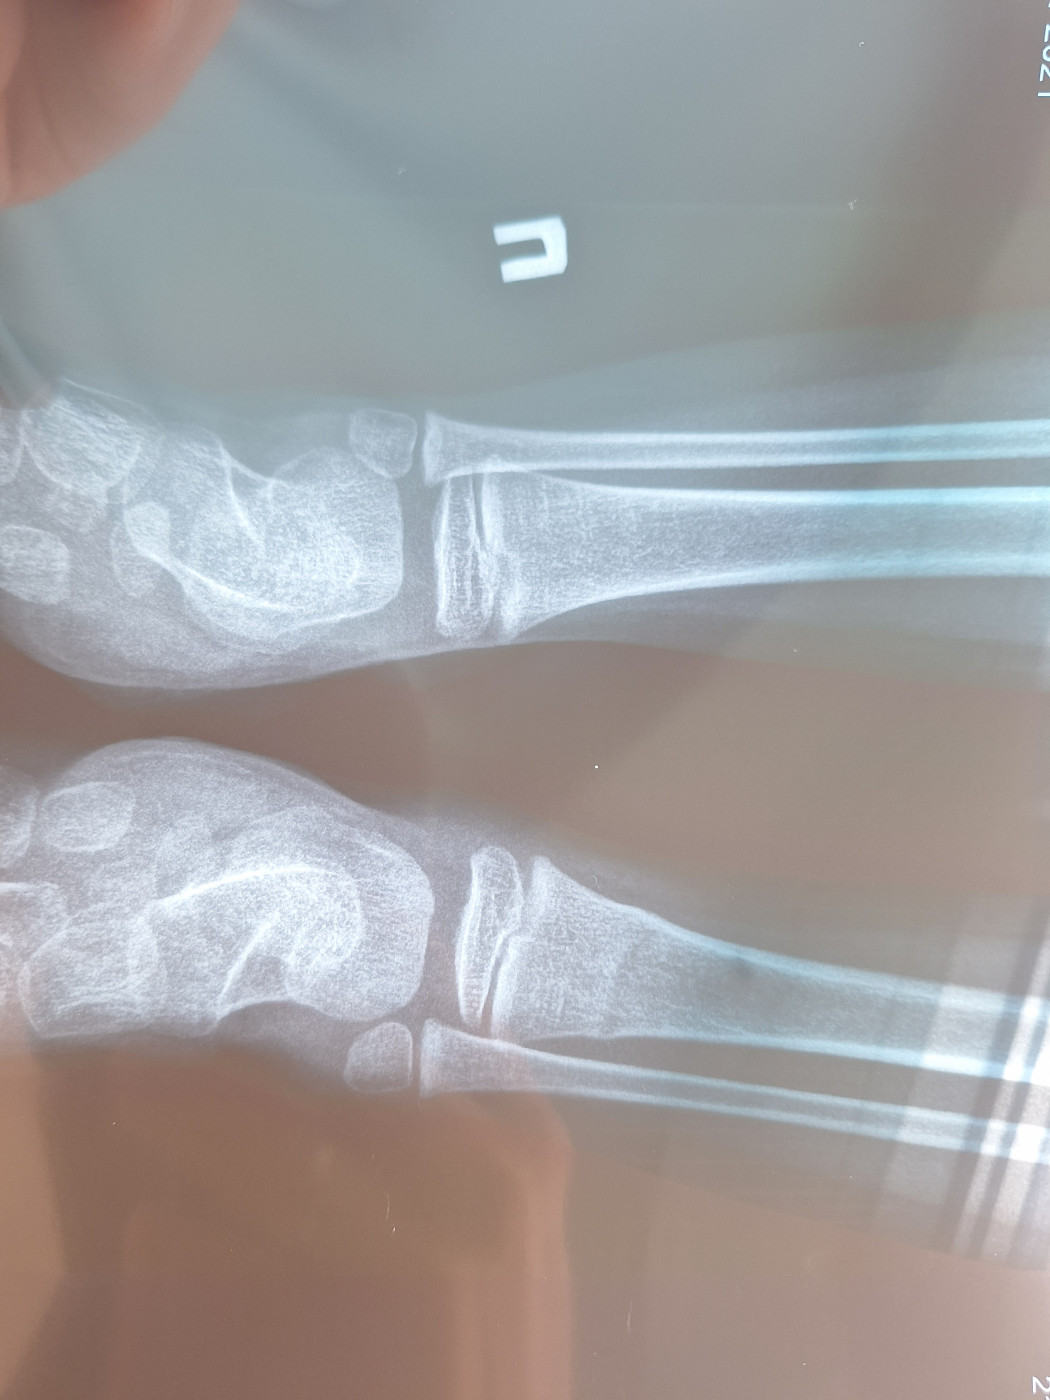

Ребенок 4 года сломал большеберцовую кость   1 ответ

21.06 упал на велосипеде и сломал ножку. Диагноз: поднакостный перелом дистрального метафиза левой большеберцовой кости.

Манипуляции: наложение гипсовой повязки. От бедра до пальцев. Фиксация 4 недели.

Повторный рентген через неделю.

Т.е перелом по типу «зеленой веточки».

Скажите пожалуйста:

1) не повреждена ли зона роста ?

2) не понятно , есть ли смещение?

3) если дай Бог , снимем гипс, то дальше какая реабилитация?